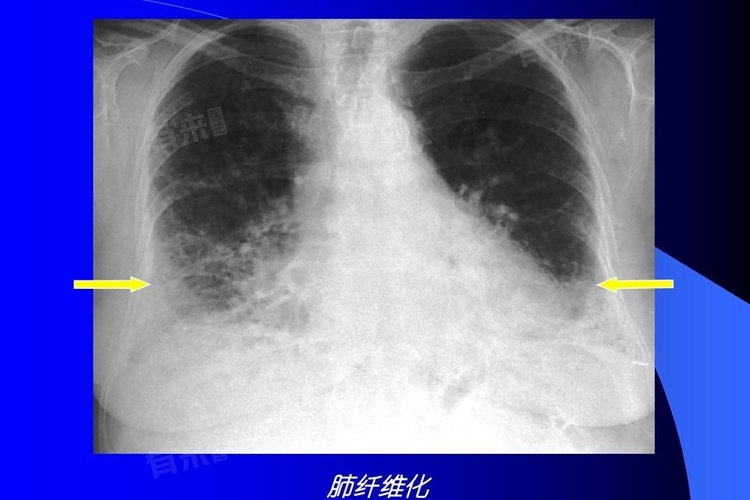

肺部纤维化会引发一系列症状,早期多表现为咳嗽,常为持续性干咳,随后活动耐力下降,日常活动易感疲劳,进而出现呼吸困难,且随病情发展逐渐加重,少数患者还会有胸痛等表现。

1、咳嗽:肺部纤维化过程中,肺组织结构改变,炎症刺激气道,引发咳嗽反射。早期多为持续性干咳,是肺部自我防御机制的一种体现。炎症因子刺激气道黏膜上的感受器,信号传递至大脑咳嗽中枢,引发咳嗽。这种咳嗽常不伴有咳痰,容易在安静时凸显,干扰患者日常生活。

2、活动耐力下降:随着肺部纤维化进展,肺的弹性降低,气体交换效率变差。身体在日常活动时,需氧量增加,但肺部无法充分提供足够氧气。肌肉得不到充足氧供,代谢产生的乳酸等物质堆积,导致疲劳感加剧。原本轻松的活动,如爬楼梯、步行稍远距离,都会变得吃力,患者活动耐力明显下降。

3、呼吸困难:病情加重,肺部纤维化范围扩大,肺的通气和换气功能严重受限。空气进出肺部受阻,氧气难以进入血液,二氧化碳排出不畅。患者主观上感觉呼吸费力,起初可能在剧烈运动时出现,逐渐发展为安静状态下也呼吸困难。呼吸频率加快、深度变浅,以维持机体最低氧需求。

4、胸痛:部分肺部纤维化患者会有胸痛症状,这是由于纤维化病变累及胸膜,或肺组织牵拉周围神经所致。胸膜受到炎症刺激,神经末梢传递疼痛信号。胸痛程度轻重不一,可为隐痛、刺痛或胀痛,发作无明显规律,增加患者痛苦,严重影响生活质量。

肺部纤维化症状逐渐显现且加重,对患者生活影响巨大。若察觉上述症状,应及时就医检查。日常要注意避免接触粉尘、烟雾等环境,戒烟。早发现、早干预,有助于延缓病情发展,改善生活质量。